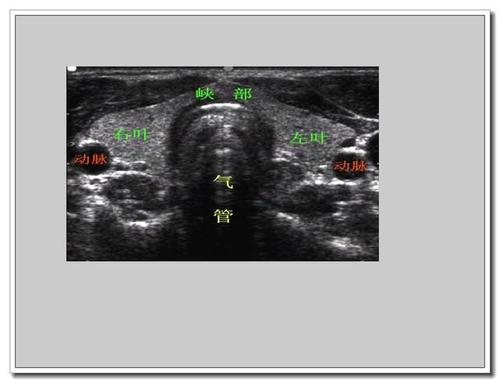

甲状腺超声

甲状腺超声,甲状腺超声图像

教你正确解读甲状腺超声的7种常见影像

超声入门正常甲状腺超声表现

常见甲状腺疾病的超声诊断:解剖,声像图及正常值

甲状腺超声图像

甲状腺超声测量示意图

甲状腺超声正常值

甲状腺超声诊断

甲状腺超声标准测量图

甲状腺超声解剖